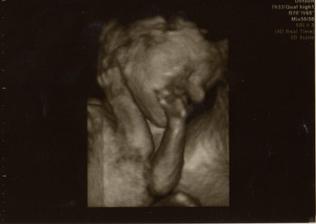

2.3.2010, 22+4tt - 3D UTZ